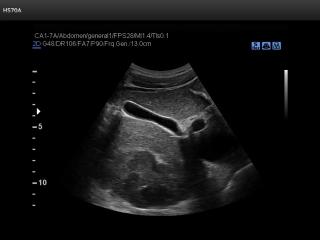

В разделе "Абдоминальные исследования" атласа представлены результаты ультразвуковых исследований органов брюшной полости. Здесь вы можете посмотреть изображения желчного пузыря, печени, почек и кишечника, эхограммы: камень в мочеточнике, внутрипеченочный кальцификат, гемангиома, спленомегалия и др.